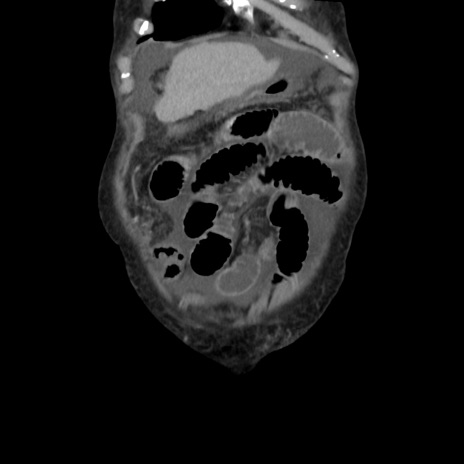

横断像